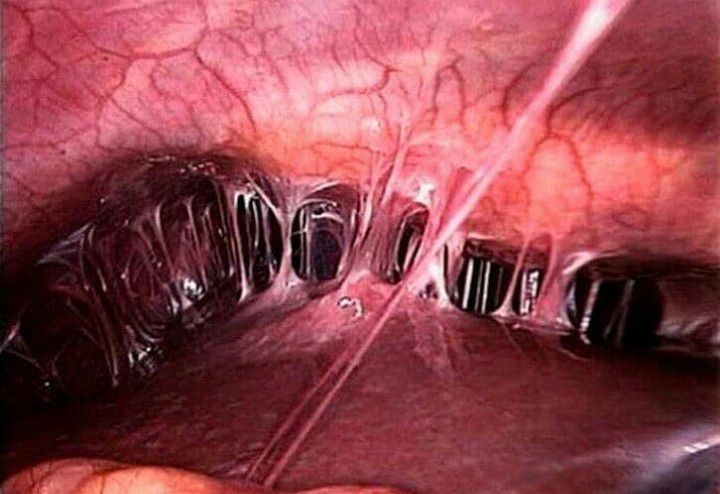

Fitz-Hugh-Curtis syndrome is an uncommon, chronic manifestation of pelvic inflammatory disease which occurs almost exclusively in women. It is characterized by inflammation of the membrane lining the stomach (peritoneum) and the tissues surrounding the liver (perihepatitis). By: https://www.instagram.com/p/CSNBtQmMq-V/?utm_medium=copy_link

Most cases of Fitz-Hugh-Curtis syndrome are linked to chlamydia or gonorrhea infections in PID. It is marked by sudden, severe pain in the upper right quadrant of the abdomen, just below the ribs. The patient may also feel pain on the right shoulder and right arm. Moving usually makes it worse. And some common symptoms like fever, chills, malaise, hiccups, headache, night sweats, diarrhoea and vomiting are also seen.